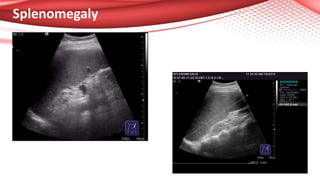

Splenomegaly

• Shen et al (1) evaluated the liver fibrosis in 324 patients with chronic viral

of early cirrhosis (for ex: the cut-off value of > 12 cm for the spleen’s

length had 0.60 sensitivity and 0.75 specificity for the diagnosis of liver

cirrhosis). But by using 2 or 3 parameters for the US diagnosis of cirrhosis

(especially the length of spleen, the diameter of splenic vein and the echo

pattern of the liver) the negative predictive value of these parameters

was close to 0.95.